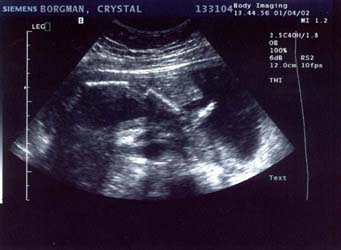

1/4/02

20 weeks

Well

it's a stubborn little bugger. The ultrasound technician

tried and tried so hard to find out the sex, bless her

heart. At the beginning she thought maybe she saw something

that would indicate it was a boy, but she wasn't even

remotely sure by any means. She said she'd check again

later and wasn't confident in the least bit that it was

actually a boy.

Later came, and

went. Baby had its legs crossed the whole time. She

also said there was a lot of umbilical cord around the

legs, so what she saw earlier may have been the cord

too. I drank a full 12 ounces of Coke before I went

in, hoping that would get the baby moving. It was moving

alright, but apparently not enough. The tech tried pushing

on my belly at all angles to get the baby to move but

it would not budge. Well I have to say I'm pretty bummed.

I've been holding out on buying clothing and stuff...

but now I know what I need to get: a whole shit-load

of gender neutral stuff. No, we will not be getting

another ultrasound so this is it until the baby's born.

On a happier note,

everything checks out ok. We saw 4 chambers in the heart

and it was beating away happily at about 142 bpm, she

said. All organs appeared to be present and looking

good. The big shocker was that the estimated weight

was 1 pound, 11 ounces. OUCH! All my pregnancy calendars

say it should still be under a pound... but maybe their

estimate was off. That does, however, help explain my

6-pound weight gain in the last month. At any rate,

all the measurements were normal and my due date remains

unchanged.

Leg (foot is on

the right, pointing up)

Large

- 682x500 pixels / 68K

Small

- 341x250 pixels / 28.8K